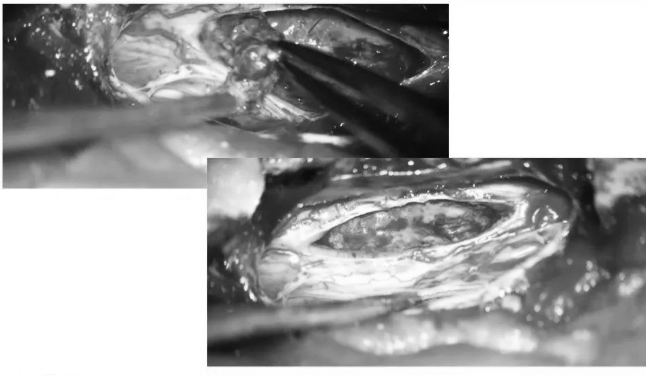

▼取下部分T5、T6椎板

▼术中超声定位海绵状血管瘤(白色)

▼术中超声显示髓内海绵状血管瘤超出骨窗大小,向T7方向生长,继续磨除部分T7椎板,扩大暴露范围

▼沿后正中切开,即可见含铁血黄素沉积带及陈旧性血凝块

▼用细致的双较或者剥离子沿含铁血黄素沉积带,分离海绵状血管瘤并电凝切断供血分支血管

▼逐步显露血管瘤腹侧面

▼血管瘤完整取出

▼测量瘤腔大小,明确肿瘤全切

▼用Proline缝线间断缝合软脊膜,封闭瘤腔,水密缝合硬脊膜